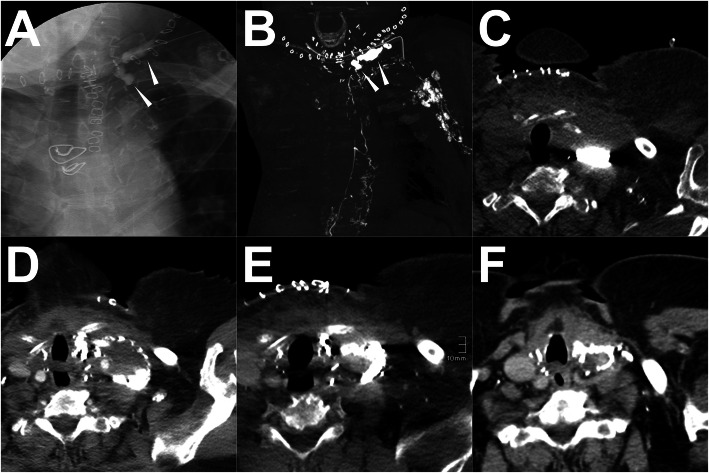

Fig. 1.

Illustration of the iodized oil-based LAG and post-LAG CT performance. Note: A patient with occurring persistent postoperative LF in the right groin after endovascular artery repair for an infrarenal abdominal aneurysm through the right femoral artery route. In the iodized oil-based LAG procedure, a total of 15 ml of lipiodol was injected with a velocity of 1 ml/min. However, due to the slow outflow of the lipiodol, 20 min after the accomplishment of the injection, the lipiodol only went up to the middle third of the thigh (black arrowhead) under the fluoroscopy and no obvious extravasation was found (a). 4 h later, the post-LAG CT was sequentially performed. The coronal (b) and sagittal (c) MIP images show definite extravasation of lipiodol (white arrowhead) at the right thigh with at least two points. The 3D-VR image (d) clearly visualized the major flowing route of the lymphatic fluid from calf to groin (white arrow) and the LF points (white arrowhead). Besides, abnormal lymphatic collateralization in calf could be observed (d). Abbreviations: LF – lymphatic fistula; LAG – lymphangiography; post-LAG CT – post-lymphangiographic computed tomography; MIP – maximum intensity projection; 3D-VR – three-dimensional volume rendering; LVs – lymphatic vessels